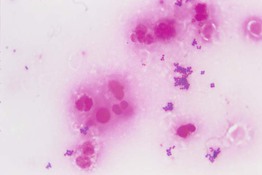

• The roof is retracted and scraping of the base and angles of the vesicle should be performed in order to obtain virally infected keratinocytes, which are thinly spread onto a glass slide, allowed to dry, and then stained with Giemsa stain (Figs. 2.6 and 2.7).

Fig. 2.6 Demonstration of location of virally infected keratinocytes in vesiculobullous lesions of herpes simplex, varicella, and herpes zoster. A Histologically, viral changes (e.g. multinucleated giant cells) are seen at the base of the vesicle; note their absence on the roof. B Scraping of the base of the vesicle is performed after the roof of the blister is reflected. A, Courtesy, Lorenzo Cerroni, MD.

Fig. 2.7 Tzanck smear demonstrating multinucleated giant cells. Such cells are seen in herpes simplex, varicella, and herpes zoster viral infections (Giemsa stain). Courtesy, Louis Fragola, MD.